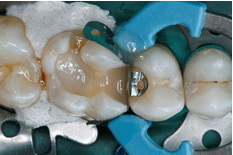

Afb. 7: Met het tweede increment van het modelleerbare Bulk-Fill-ormocer Admira Fusion x-tra werd de resterende ruimte van de caviteit compleet gevuld.

Afb. 8: Eindsituatie: Definitief uitgewerkte en hoogglans gepolijste ormocerrestauratie. De functionaliteit en esthetiek van het element zijn weer hersteld.